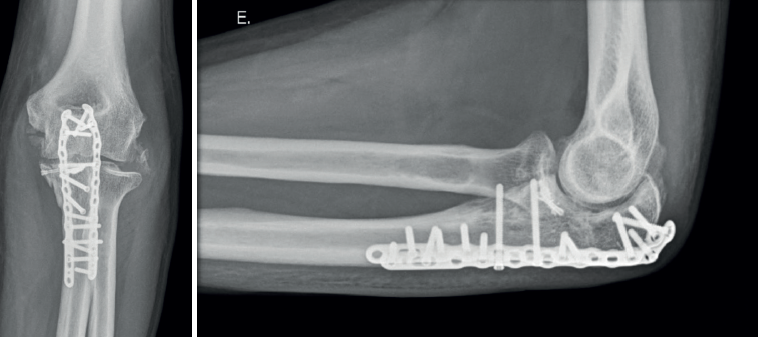

- Tipo III. Las fracturas basilares grandes suelen formar parte de una fractura-luxación del olécranon; por tanto, en todos los casos precisarán tratamiento quirúrgico. Podremos sintetizarlas directamente con un tornillo desde la placa posterior de osteosíntesis del cúbito y añadir tornillos interfragmentarios o canulados si es necesario (Figura 6). La reducción de los fragmentos conviene hacerla de forma secuencial, preferiblemente de distal a proximal. A veces precisan una placa medial adicional. Si hay un único fragmento grande, también se pueden fijar con un tornillo insertado de anterior a posterior.